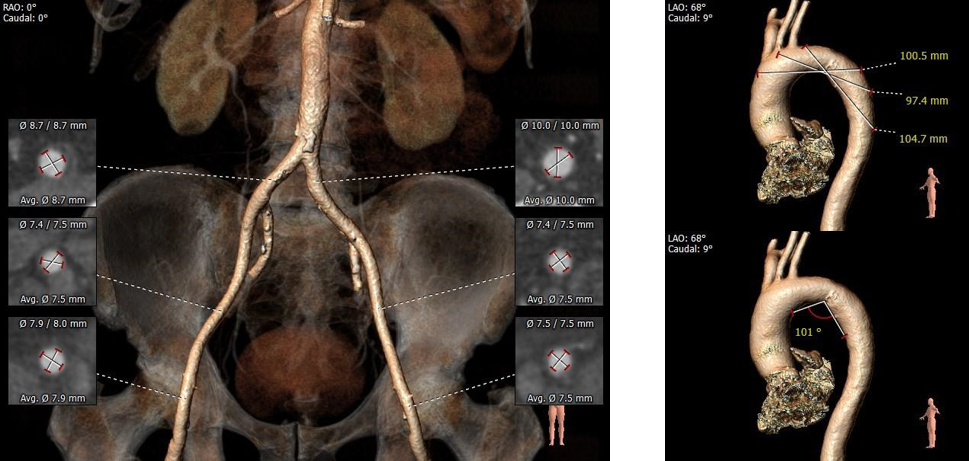

血管入路评估: